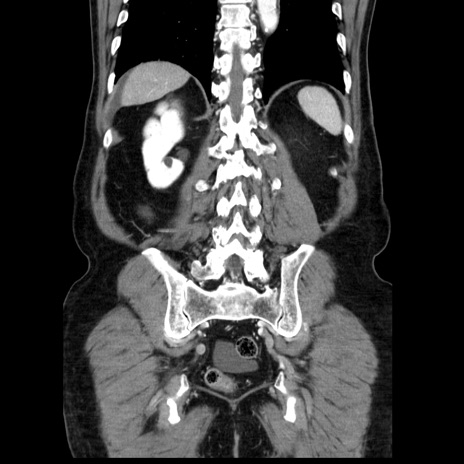

症例30(冠状断像)

【症例】80歳代男性

【主訴】臍周囲痛

【現病歴】約6時間前から臍下部痛が出現。次第に腹部膨隆・背部痛も生じてきたため来院。背部痛の場所は変化しない。

【身体所見】意識清明、BT 36.3℃、BP  131/87mmHg、P 87bpm、SpO2 100%(RA)、臍周囲自発痛・圧痛あり、反跳痛なし、自発痛部位に一致して板状硬あり、腹部膨隆、腸雑音減弱、CVA tenderness両側陰性。

【データ】WBC 19600、CRP 0.33